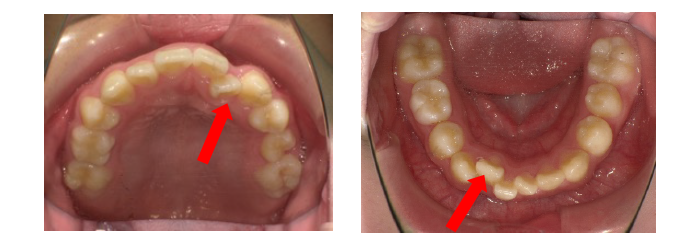

診断名は、 上下顎前歯叢生(そうせい)です。

(模型を見てみると)

■歯の大きさ